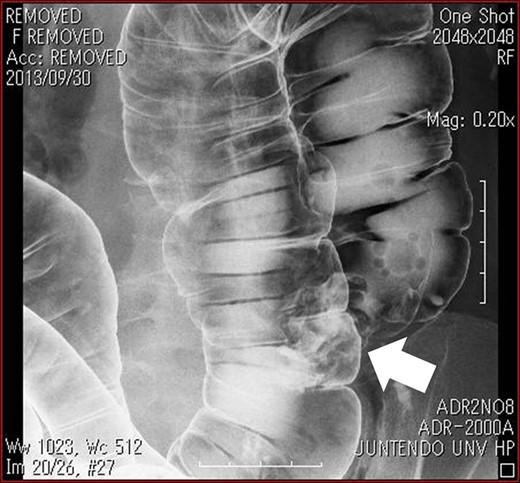

A 76-year-old woman known since early childhood to have situs inversus totalis was referred to the Breast Surgical Department for left breast cancer. She underwent F-fluorodeoxy-glucose positron emission tomography-computed tomography (FDG-PET/CT), because of high level of carcinoembryonic antigen (CEA). PET/CT image showed FDG uptake at the ascending colon (Fig. 1). Therefore, we were consulted by the doctor of Breast Surgical Department. The patient was admitted to our department for further evaluation and surgical treatment. And the treatment for the colon cancer preceded the treatment for breast cancer because of advanced stage of the colon cancer.

PET/CT image showed FDG uptake at the ascending colon (arrow).